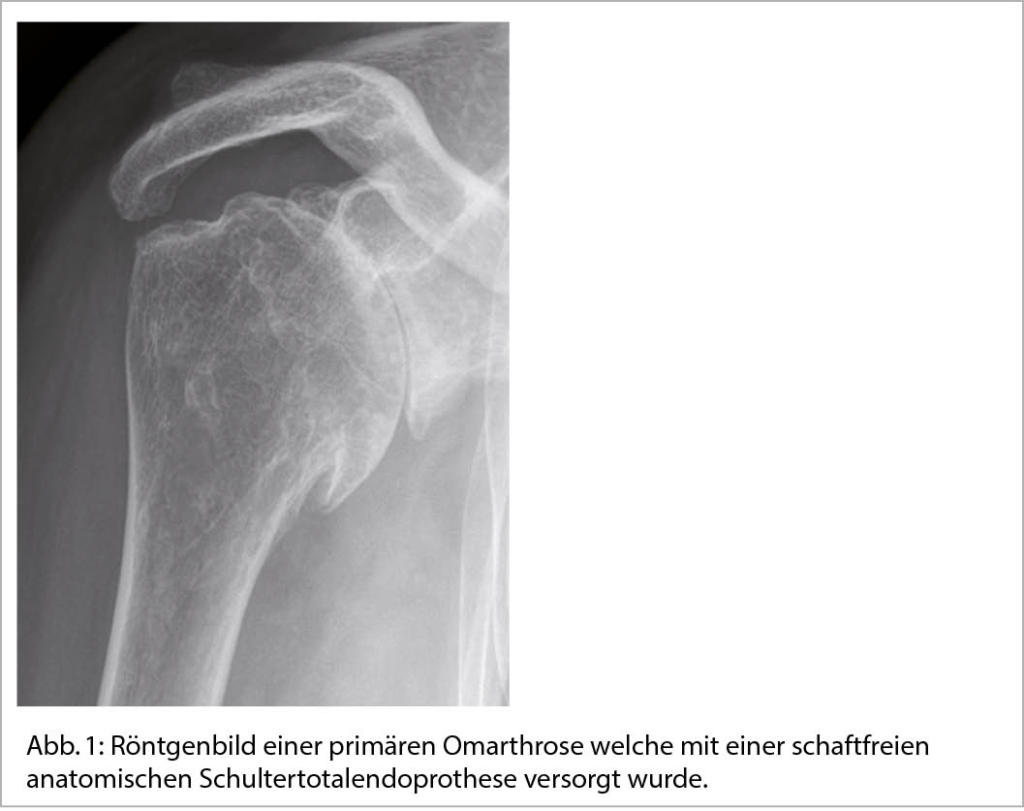

Schulterbeschwerden sind der dritthäufigste Vorstellungsgrund unter den muskuloskelettalen Beschwerden in der primären Gesundheitsversorgung. In 21% der durch den Hausarzt aufgrund von persistierenden Schulterschmerzen überwiesenen Patienten wird in der radiologischen Bildgebung eine Omarthrose diagnostiziert (1). In Zweidrittel der Fälle liegt den degenerativen Veränderungen des Knorpels und des angrenzenden Knochens sowie des periartikulären Weichteilgewebes kein spezifischer Auslöser zugrunde. Die Prävalenz dieser sogenannten primären Arthrose steigt mit zunehmendem Alter. Während 15% bereits in der 6. Lebensdekade betroffen sind, steigt der Anteil bei Patienten über 70 Jahren auf über 25% (2). Beeinflussbare Risikofaktoren für die primäre Arthrose stellen Übergewicht, Rauchen sowie systemische Erkrankungen wie arterielle Hypertonie dar (Abb. 1) (3).

Die Schultergelenksarthrose kann in eine primäre Arthrose und eine sekundäre Arthrose eingeteilt werden. Während bei der primären Arthrose mit Ausnahme des eventuell höheren Alters und des damit einhergehenden Verschleisses keine eindeutige Ursache genannt werden kann, ist die sekundäre Arthrose auf einen klaren Grund zurückzuführen der eine frühzeitige Degeneration des Schultergelenkes auslöst. Stellt sich in der Anamnese und in der klinischen Untersuchung der Verdacht einer Schultergelenksarthrose, benötigt man zur weiteren Diagnostik eine Bildgebung in Form von Röntgenaufnahmen. Initial steht eine schmerzlindernde Kortisoninfiltration und anti-entzündliche medikamentöse Therapie im Vordergrund, welche durch physiotherapeutische Massnahmen begleitet werden sollte. Bei therapierefraktären Beschwerden und grossem Leidensdruck besteht die Indikation zur operativen Versorgung mittels einer Schulterendoprothese. Hierdurch kann sowohl im kurz- sowie langfristigen Verlauf eine deutliche Schmerzreduktion und Funktionsverbesserung erzielt werden und somit die Lebensqualität der Patienten verbessert werden. Zeigt sich eine fortgeschrittene Dezentrierung des Oberarmkopfes oder ein instabiles Drehzentrum ist die Versorgung mittels einer inversen Schulterendoprothese indiziert. Moderne Planungsverfahren erlauben die individuelle Anpassung der Schulterendoprothese an die individuelle Anatomie des Schulterblattes und Oberarmkopfes sowie die Körperhaltung der Patientinnen und Patienten.